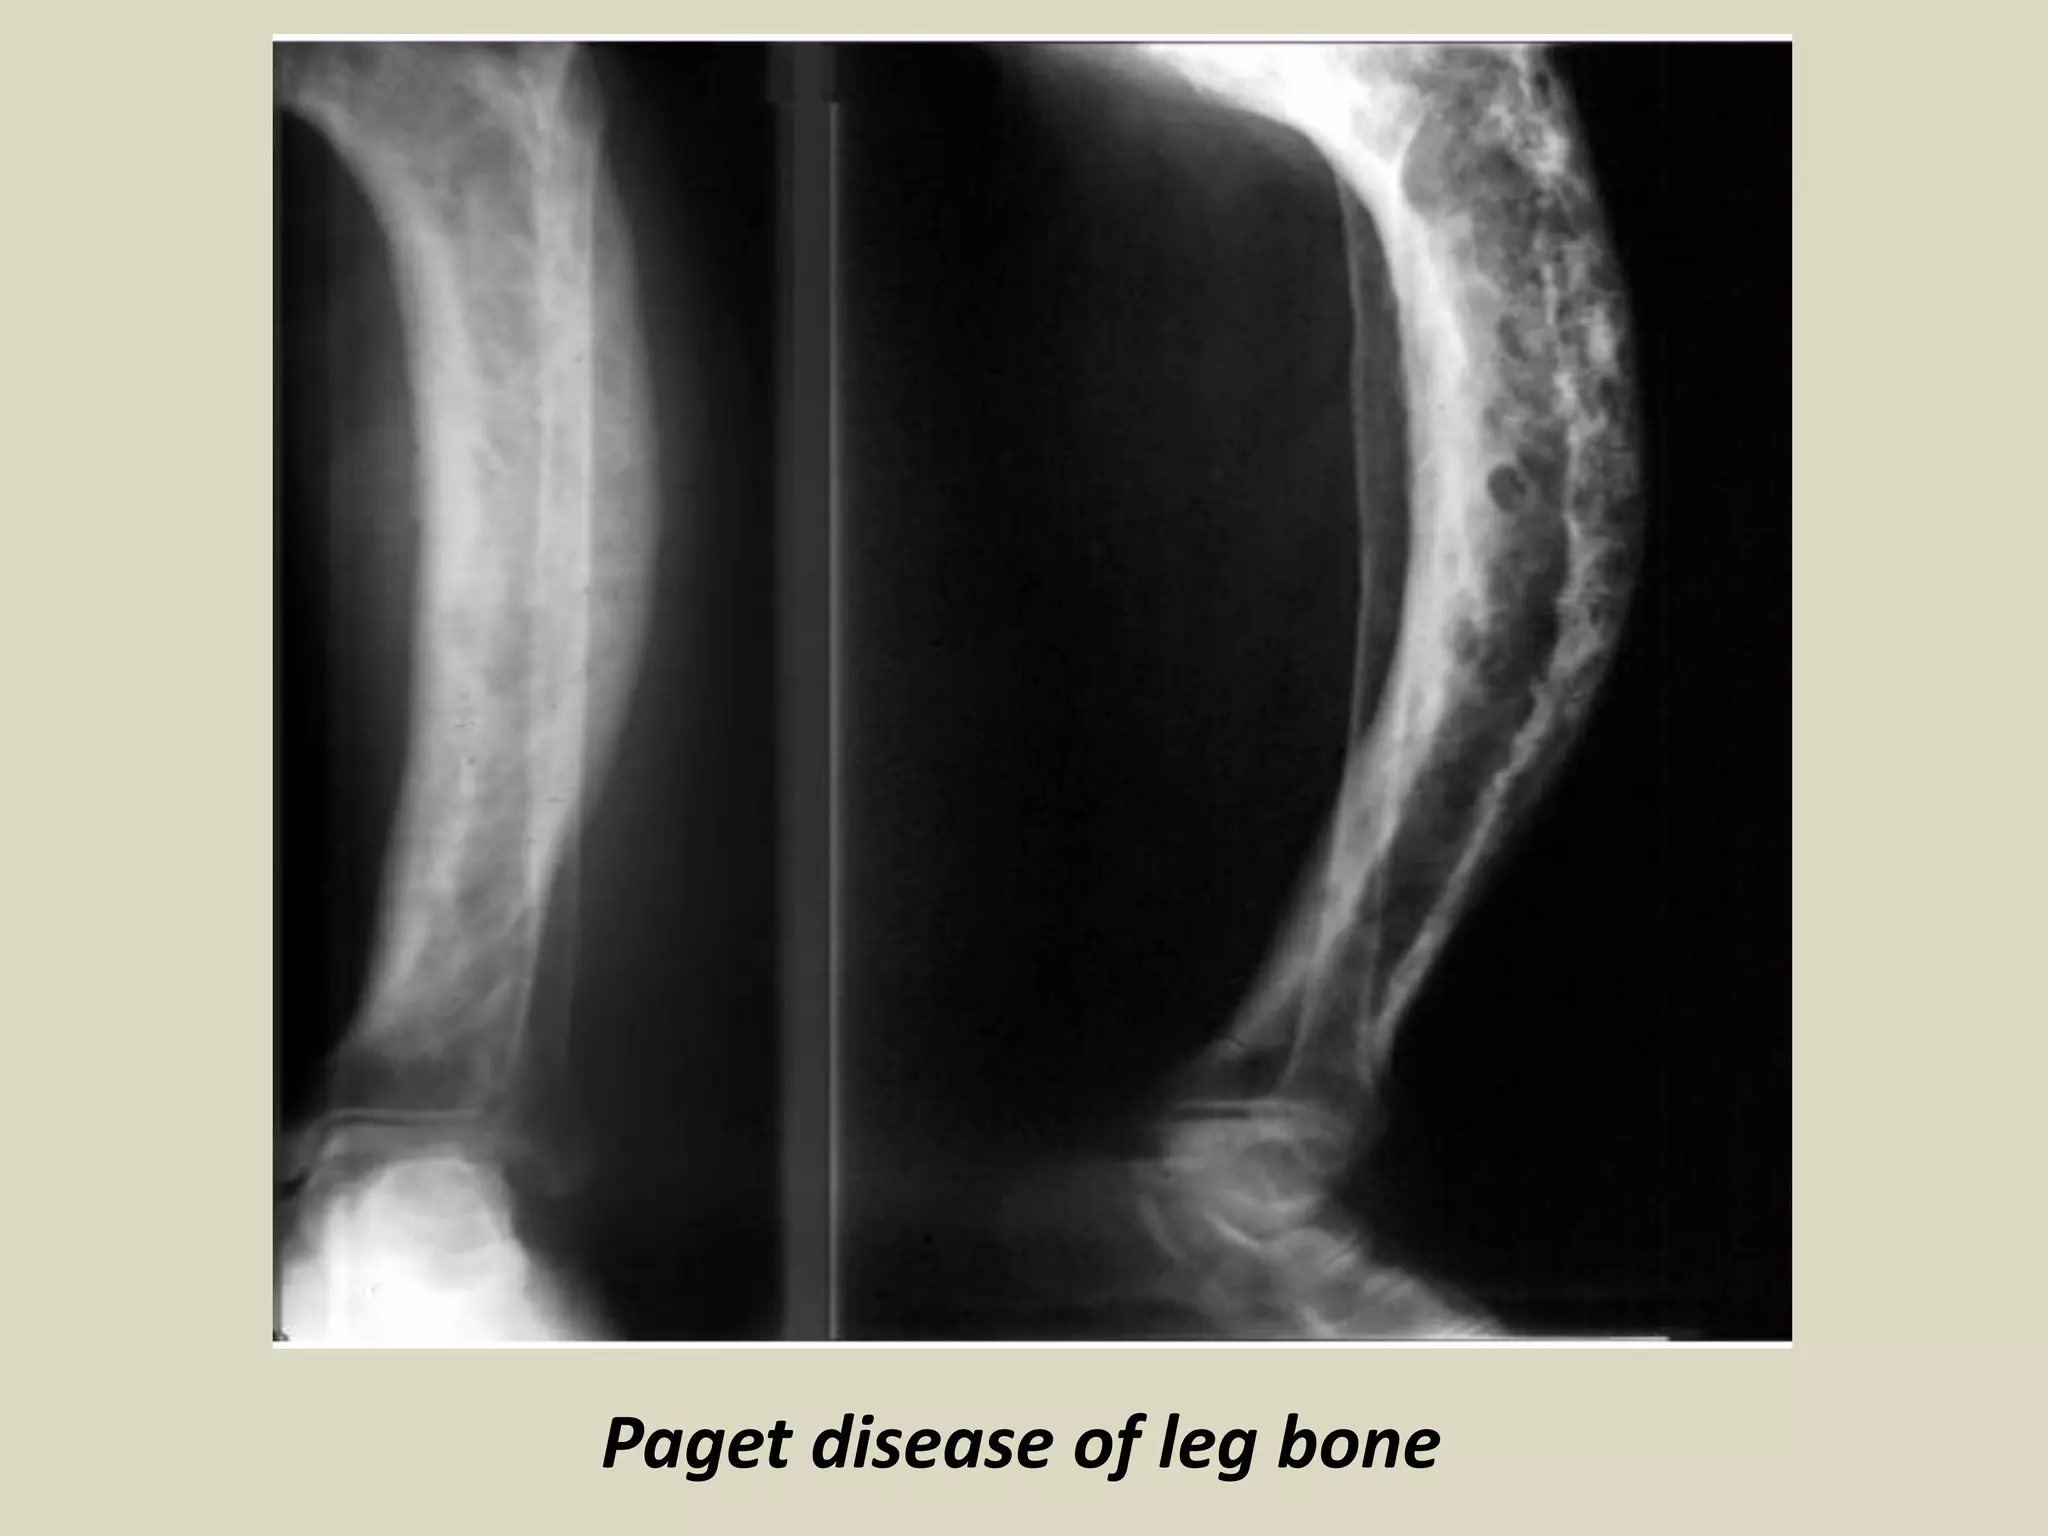

Paget disease of leg bone